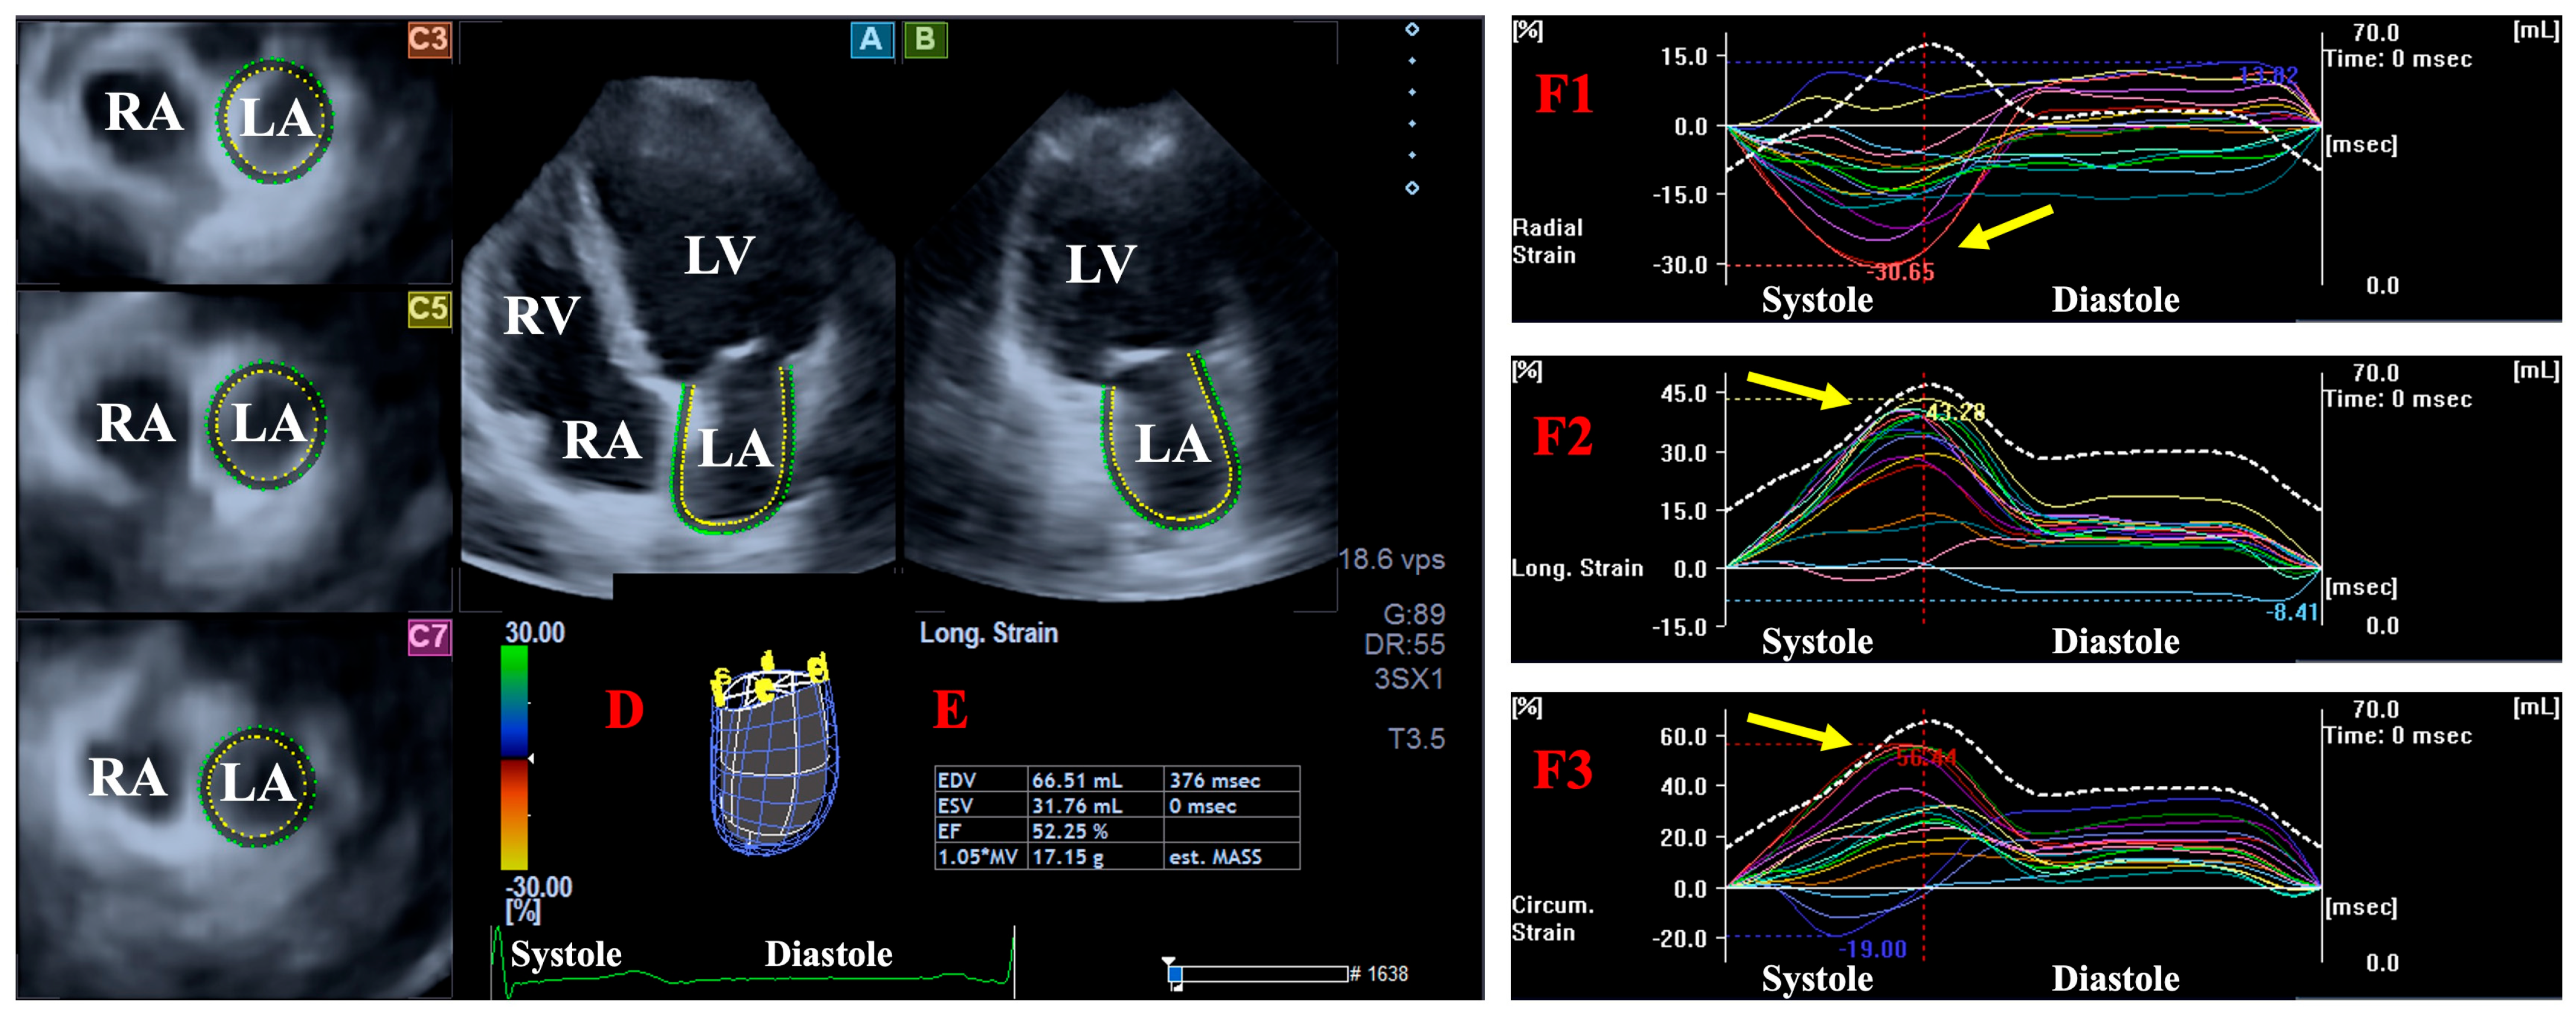

2.4. DSTE-Derived LA/LV Volumes and Strains

- LA/LV radial strain (LA/LV-RS), featuring the thinning/thickening of the myocardial tissue.

- LA/LV circumferential strain (LA/LV-CS), featuring the widening/narrowing of the myocardial tissue.

- LA/LV longitudinal strain (LA/LV-LS), featuring the lengthening/shortening of the myocardial tissue.